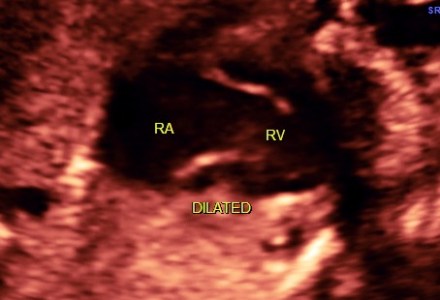

Hypoplastic Left Heart Syndrome (H.L.H.S.)